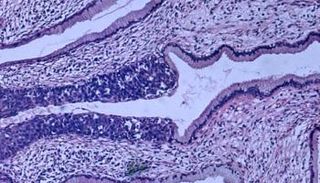

فيروس الورم الحليمي البشري، هو أكثر الأمراض التي تنتقل عن طريق الاتصال الجنسي شيوعاً في الولايات المتحدة.